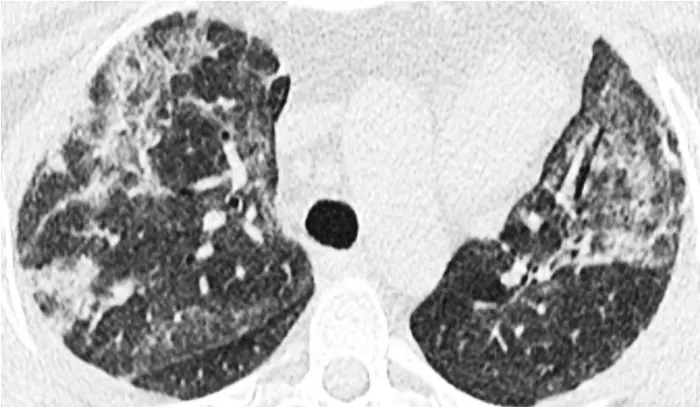

The study began with McGonagle lab’s detection of autoantibodies to MDA5 — an RNA-sensing enzyme whose functions include detecting COVID-19 and other RNA viruses. A total of 25 patients from the group of 60 developed lung scarring, also known as interstitial lung disease. Ghosh noted that the lung scarring was bad enough to cause eight people in the group to die due to progressive fibrosis. She said that there are established clinical profiles of MDA5 autoimmune diseases.

“Interleukin-15 is a cytokine that can cause two major immune cell types,” she explained. “These can push cells to the brink of exhaustion and create an immunologic phenotype that is very, very often seen as a hallmark of progressive interstitial lung disease, or fibrosis of the lung.”